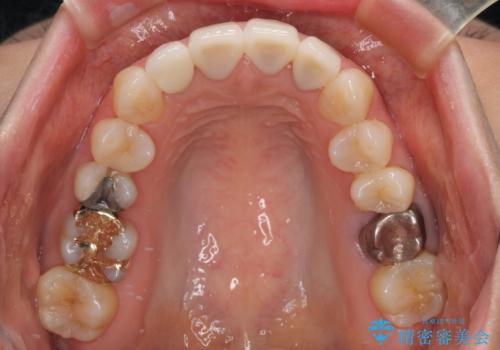

- 上顎4前歯に装着されているセラミッククラウンのうち、ひとつが欠けてしまったとのことで来院された患者様です。

土台となっている歯には問題がないため、周囲のセラミッククラウンと色調が合うように、オーダーメイドタイプのセラミッククラウンにて補綴治療を行うこととしました.

欠けてしまったセラミッククラウンはガラス系セラミッククラウンであったため、今回製作する歯は、強度の強いジルコニアセラミッククラウンとしました。

クラウンの種類は異なりますが、色調の適合したクラウンを装着することができました。